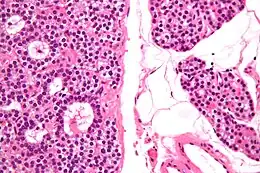

Adénome parathyroïdien en microscopie optique